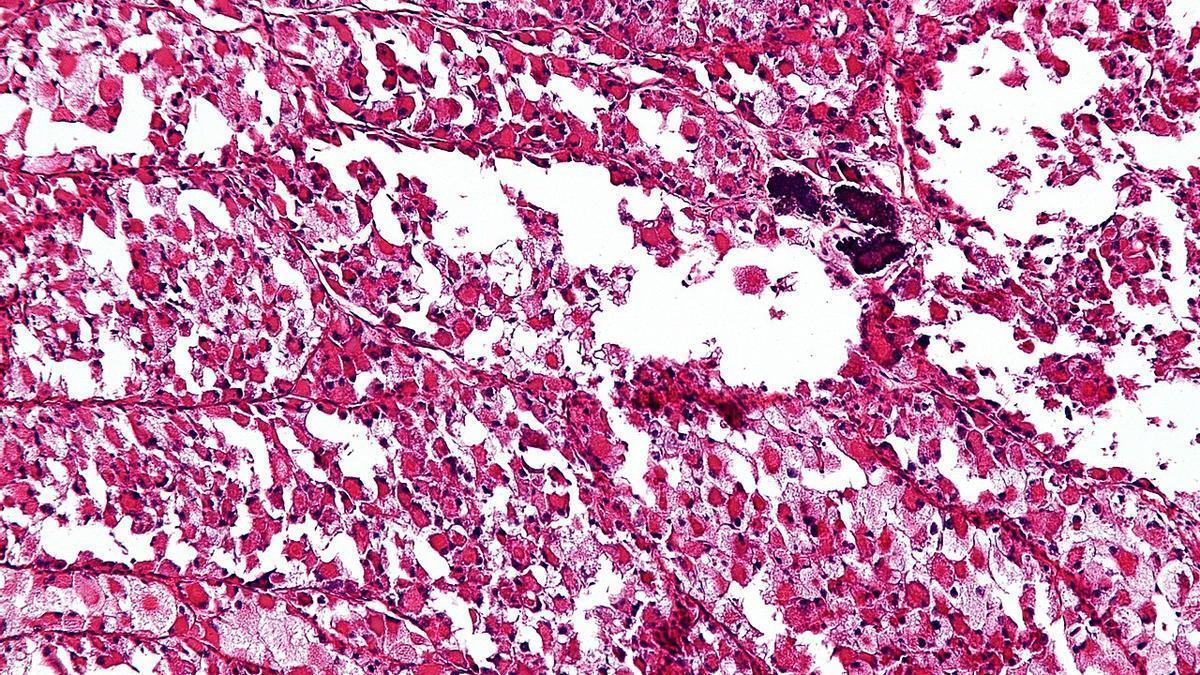

Sarcoma: así se detecta un cáncer poco frecuente, silencioso y que puede acabar en amputación de extremidad / NEPHRON

Su frecuencia es excepcional, diagnosticándose entre cuatro y cinco casos por cada 100.000 habitantes al año. Afecta tanto a huesos como a tejidos blandos y hay más de 75 subtipos, que, a su vez, se dividen en sarcomas de partes blandas, suponiendo el 85 %, y óseos, que representan el 15 %.